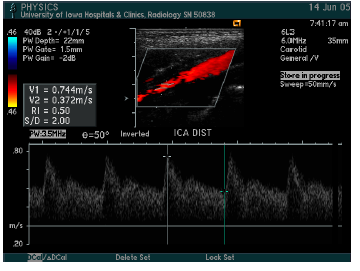

what vessel is this waveform likely from?

CCA (below is distal CCA)

ICA (proximal), below is distal